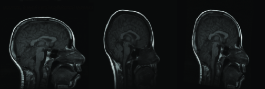

The algorithm is performed both on image scale and on standard intensity scale. Thirty deformed brain images are generated by applying random deformations to the original target images. Original source images are tried to be registered to each deformed target images on standard intensity scale and image scale. Random deformations are obtained by randomly choosing parameters for affine matrix A𝐴A. The resulting deformation field is normalized so that r.m.s displacement is at most 12 pixels. An example for affinely warped images is shown in Figure 6.

Figure 6: Images are randomly deformed by affine transformations

Refer to caption

where [x,y]𝑥𝑦[x,y], [x,y]superscript𝑥superscript𝑦[x^{\prime},y^{\prime}] are initial and transformed spatial coordinates of the images respectively, and, n1,..n8n_{1},..n_{8} are chosen randomly such that r.m.s displacement is at most 12 pixels. An example for nonlinearly warped images is shown in Figure 8.

Figure 8: Images are randomly deformed by nonlinear transformations